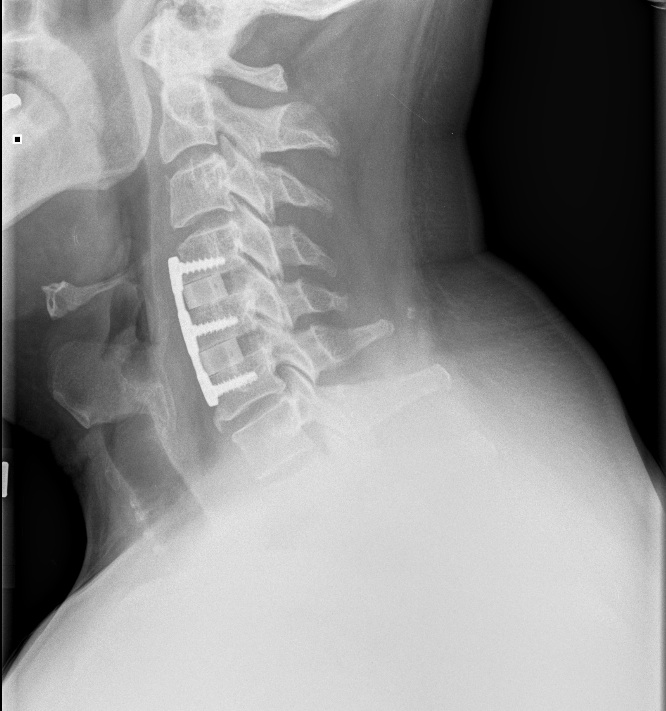

Saw my surgeon today with fresh X-rays. (below)

He likes how it is looking, wants to see me again in three months, at which time we'll discuss my return to flying. Thus grounded for the summer, I'll have to miss Hyner this weekend and July 4th.

Wow, Cragin, those are some impressive x-rays. Hope you can make it out to Hyner for Labor Day.

Getting just a wee bit intimate, are we Cragin?

Naw, how can anything from the neck up be that intimate?brianvh wrote:Getting just a wee bit intimate, are we Cragin?

Well, I guess I have given proof positive that I've been permanently screwed.

Neck up?! That first picture had me thinking I was looking at lower back and thigh...I'm not titillated anymore at all!